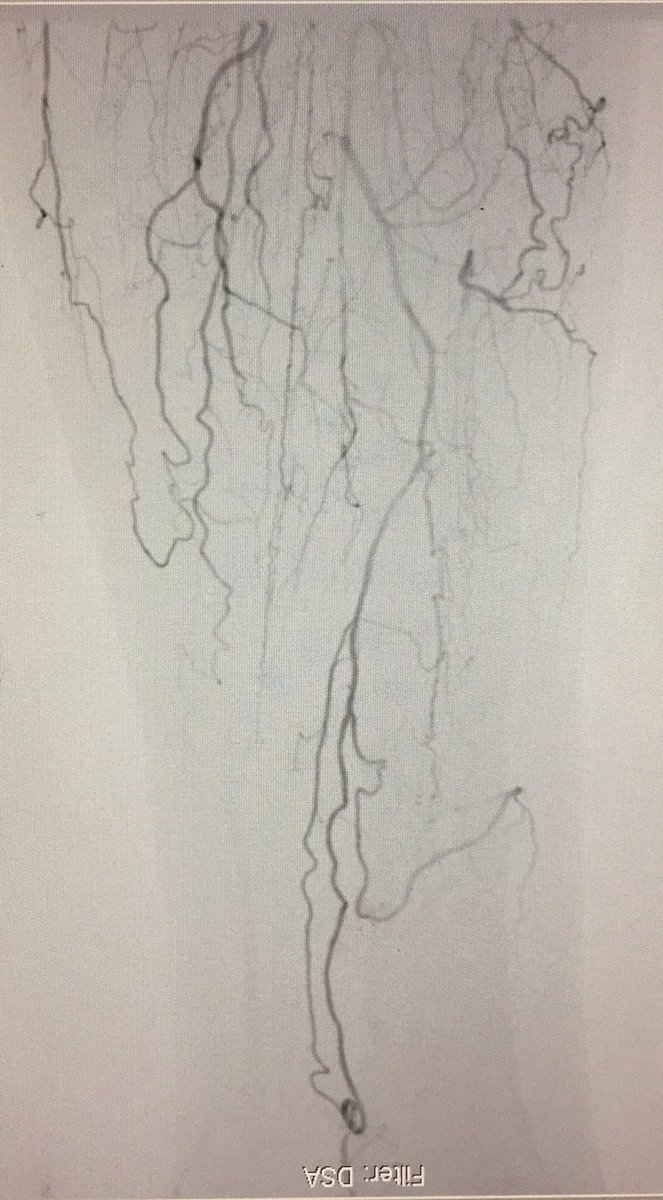

An image is worth a 1,000 words - what does this one depict ? Participate in quiz here🔗pcronline.com/Cases-resource…

🖼️submitted by Eirini Dri, Sofia Vaina, Anastasios Milkas, Konstantinos Tsioufis from 🇬🇷 and selected for #EuroPCR

#interventionalcardiology #cardiotwitter